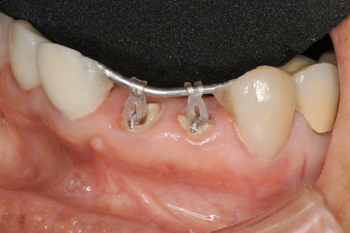

右の前歯二本がボッキリおれてしまいました。幸い歯の根っ子は折れていませんでしたから、抜歯せずに残せそうですが.........

歯が折れて根っ子が少しだけ歯茎からでている状態。